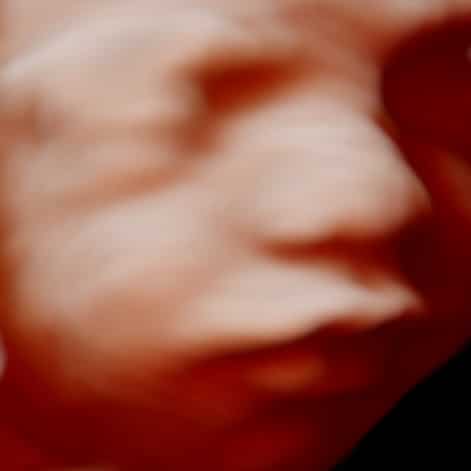

Bij een 3D echo wordt er kleur en diepte aan de 2D echo toegevoegd. 3D staat voor drie dimensionaal. Je ziet dan de lengte, breedte en diepte van het echobeeld. Het grootste verschil tussen de 2D echo en de 3D echo is dat de 2D echo, de lengte of doorsnede van het kindje laat zien terwijl je bij 3D net als wij nergens doorheen kijkt, maar erom heen.

Dit betekent dat alles wat ook voor het gezichtje ligt op de 3D echo gezien wordt. Zoals b.v. armpjes of voetjes. De 3D beelden zijn stilstaand net als foto’s. De 3D pretecho is mooi tussen de 24 en 32 weken.

Men spreekt van een 4D echobeeld als het 3D beeld beweegt, bijvoorbeeld als het kindje zwaait of gaapt. Tegenwoordig zie je een combinatie van 3D met 4D echobeeld. Dit noemen we ook wel “live 3D”. Het bewegende kindje is de vierde dimensie. Tijdens de 4D pretecho zie je het kindje afwisselend in 2D zwart wit en 3D gekleurde beelden. Dit noemen we ook wel ‘Realistic View”. Voor het verkrijgen van mooie 3/4D beelden is het noodzakelijk om eerst in 2D het kindje mooi in beeld te krijgen alvorens over te schakelen naar het 3/4D beeld.

De 3D/4D echo is ook mooi vroeg in de zwangerschap als je het meeste van het kindje op de echo wilt zien. Echter unieke kenmerken van het kindje worden vanaf 24 weken gezien als het kindje wat meer vet heeft ontwikkeld.